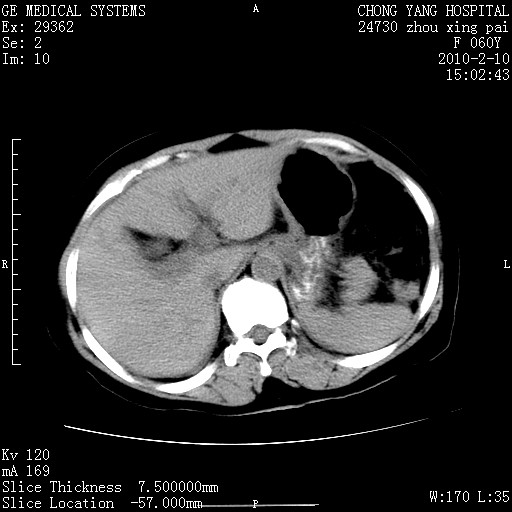

标题: CT24682:F60Y 腹痛 其它不详 [打印本页]

标题: CT24682:F60Y 腹痛 其它不详

胆总管末端梗阻!结石?胰腺影增粗,以胰腺头部为著,胰周看见渗出影,双侧胸腔积液,(胸膜反应)考虑胰腺炎。

1)胆总管末端梗阻,不排除结石所致可能。2)胰腺炎。3)慢性胆囊炎可能。4)左侧输尿管上段扩张。5)少量腹水。6)双侧少量胸腔积液,伴两下肺部分肺萎陷。

1)胆囊炎。2)胆源性胰腺炎。3)右肾周筋膜增厚,肾旁前间隙积液。4)左侧输尿管上段扩张。5)少量腹水。6)双侧少量胸腔积液,伴两下肺部分肺膨胀不全。

1)胆总管末端梗阻。2)胰腺炎。3)慢性胆囊炎可能。4)左侧输尿管上段扩张。5)少量腹水。6)双侧少量胸腔积液,伴两下肺部分肺萎陷。